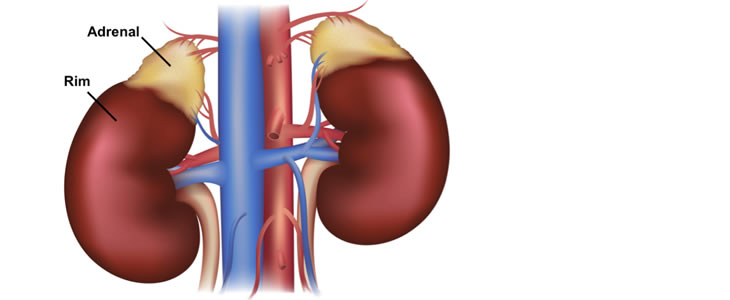

Doença das Adrenais

As suprarrenais ou adrenais são pequenas glândulas que se localizam acima dos rins. São responsáveis pela produção de alguns hormônios como o cortisol, a aldosterona e alguns hormônios sexuais como a androstenediona. Além disso, também produzem catecolaminas que são a adrenalina e a noradrenalina. Várias doenças podem ser decorrentes de alterações nas adrenais como: Síndrome de Cushing; Doença de Addison; alguns tumores benignos, produtores ou não, como Feocromocitoma, Aldosteronoma; e, mais raramente, podem ser sítio de tumores malignos. A avaliação do médico endocrinologista é fundamental para o diagnóstico e tratamento destas doenças.